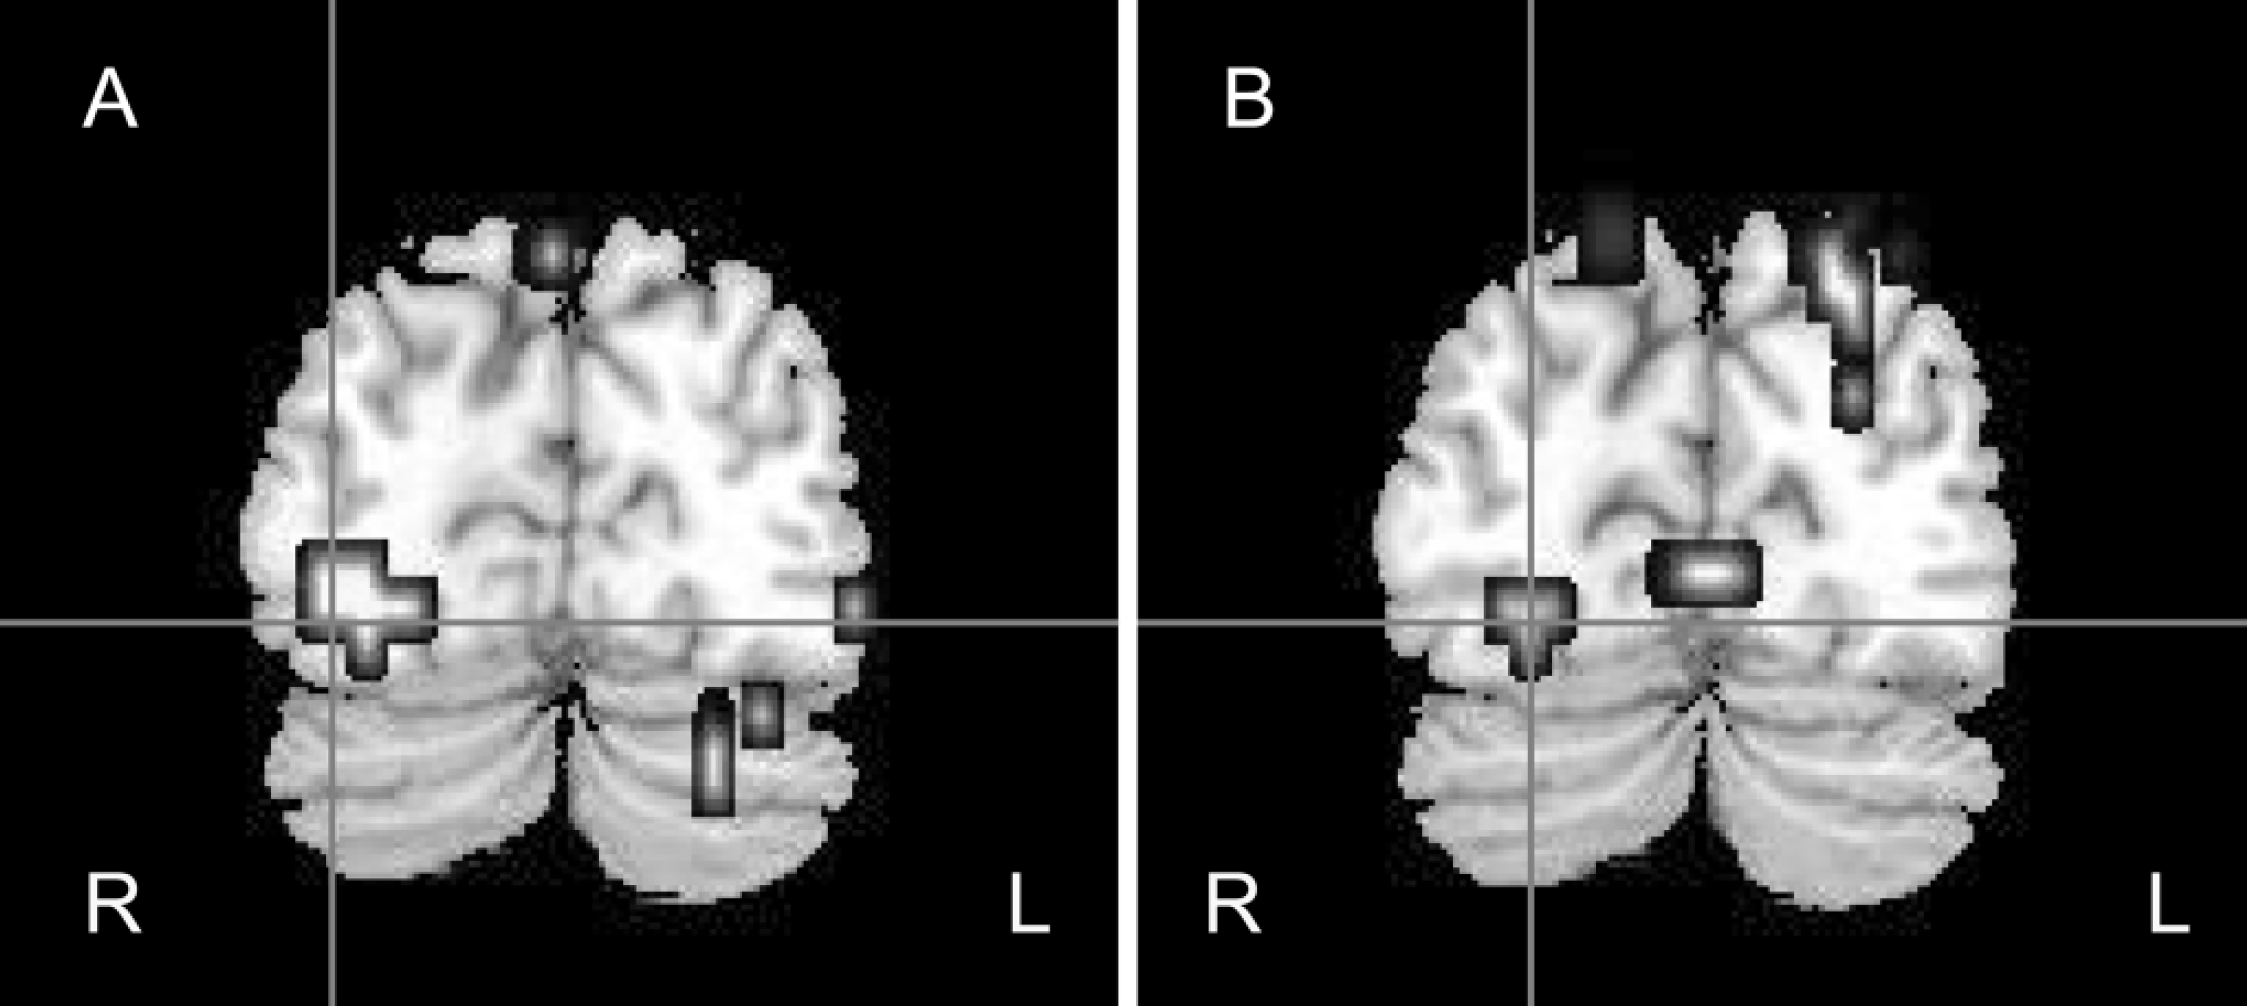

• Control group: fearful v. neutral faces. In the control group the processing of fearful faces elicited significantly greater activation within the bilateral amygdala, right-sided parahippocampal gyrus, fusiform gyrus, superior temporal gyrus, middle occipital and temporal gyri and right insula than did processing of neutral faces (Table 2; Figs 1(a), 2(a)).

Fig. 1 Coronal view of the brain showing right fusiform gyrus responses to fearful v. neutral faces (a) in the control group (x=32, y=–74, z=–13) and (b) the between-group differences, where control participants demonstrated greater activation than the participants with schizophrenia (x=25, y=–77, z=–13). R, right hemisphere; L, left hemisphere.

• Control v. patient groups: activation to fearful faces. Control participants demonstrated significantly greater activation than did the participants with schizophrenia during the processing of fearful faces within the right fusiform gyrus, the left superior temporal gyrus, the bilateral inferior frontal gyri, the right amygdala and right parahippocampal gyrus (Table 2; Figs 1(b), 2(b)).